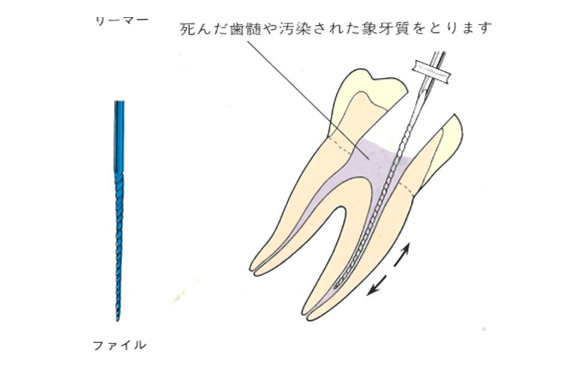

虫歯菌に侵された神経(歯髄)や汚染された象牙質をリーマー、Kファイル、Hファイルなどを使用して取り除いていきます。

ファイルやリーマーを使用して神経を取ります。